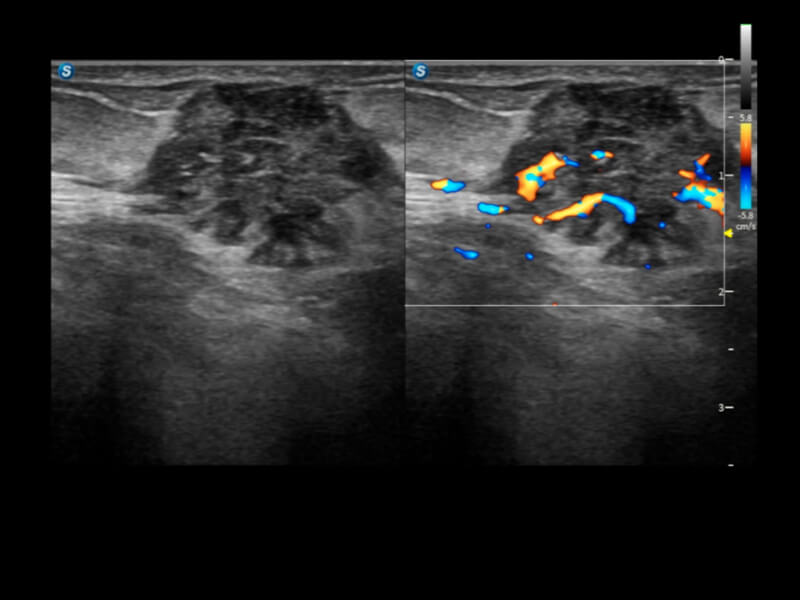

通過光照模型,使二維血流顯示出立體的效果,增加血流的敏感性、成束性,減少外溢??梢院推渌煌难骷夹g(shù)聯(lián)合使用,融合不同技術(shù)的優(yōu)勢(shì)。輕松應(yīng)對(duì)微小血管,增強(qiáng)血流的立體效果,提升視覺敏感性。